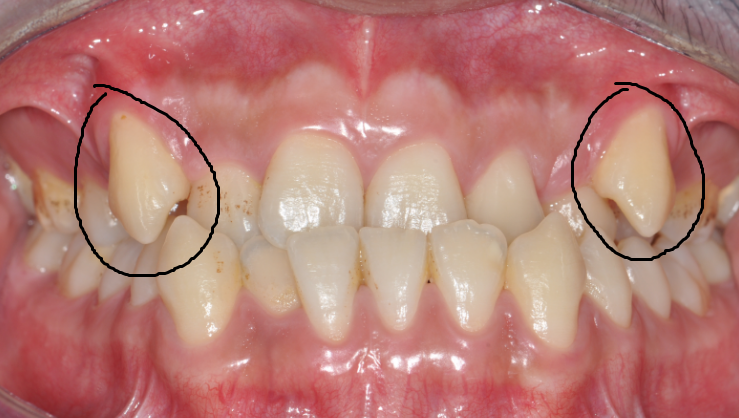

齒 嘿嘿,牙妹,我覺得我的牙齒距離就差一點兒了。你看我的虎牙,長出來的位置不正,被擠在牙弓外面,一張嘴就會看見,很不美觀。別的牙還挺齊的,所以我想能不能直接把虎牙拔掉,這樣就用簡單的方法解決了問題。(圖片1 2)